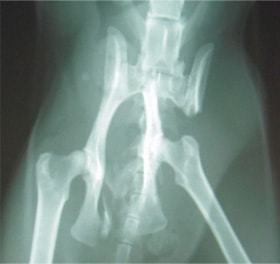

ペルシャ猫 11ヶ月齢 雄

他院にて左大腿骨遠位の成長板骨折(salter-harrisⅠ型)が認められており、治療相談を目的として来院。当院にて、キルシュナーワイヤーを用いたピンニングにより骨折部位の整復を行いました。術後の経過は良好で、現在も経過観察中です。

術前レントゲン

術後レントゲン